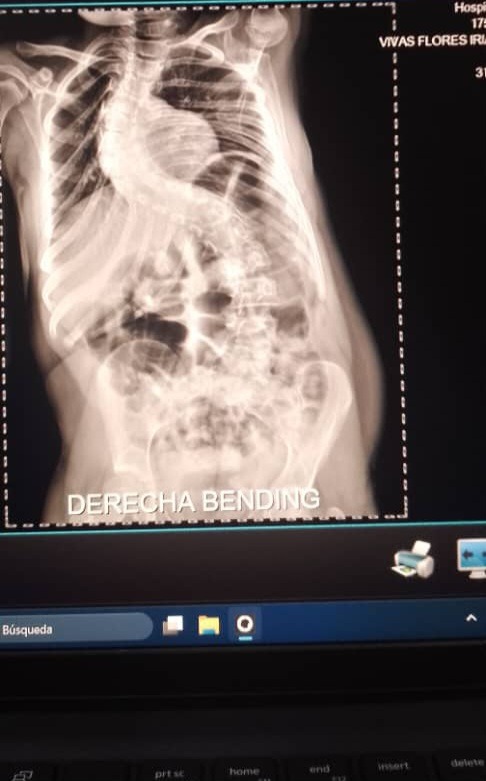

Hola me llamo iriangela y por medio de mi familiar que logró crear esta cuenta estamos recaudando fondos para mi operación, como dicen mis informes médicos padezco de escoliosis asociada a mi síndrome lo cual afecta mi columna vertebral y compromete mi calidad de vida, mis padres no cuenta con los recursos necesarios para dicha operación que se sugiere de emergencia también debo viajar a caracas y debemos cubrir gastos de comida hospedaje y transporte ya que somos del estado tachira sin familia en caracas cualquier granito de arena seria de gran ayuda para mi, de antemano gracias Dios les bendiga!